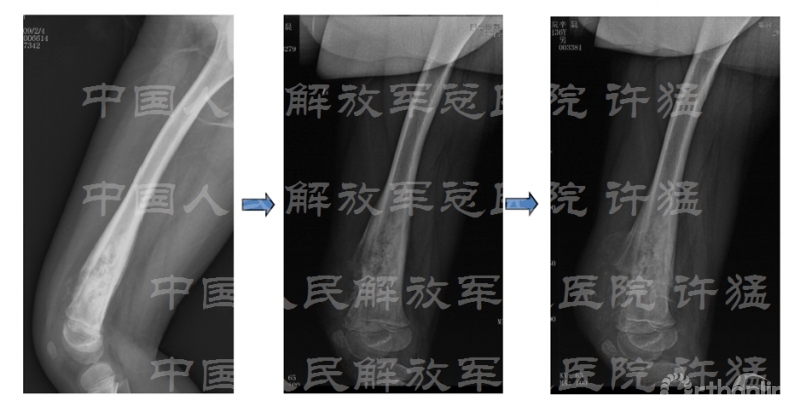

治疗前相关检查: